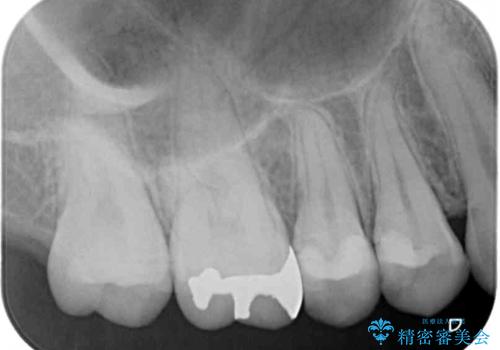

- 奥歯にフロスが引っかかるようになり、虫歯ではないかとのことで来院された患者様です。

レントゲン写真より、左右奥歯にむし歯があることが分かりました。

奥で目立たないことから、虫歯の再発リスクが最も低く、咬合力による歯への負担も少ないゴールドインレー(PGAインレー、白金加金インレー)にて修復治療をすることとしました。